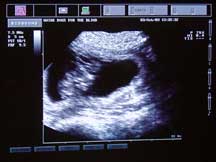

She has approximately 8 puppies inside her. This is a guess and things can change as she gets closer to her due date (Oct 30). The puppies are about an inch long. This was Alda's 5th week of pregnancy. |

These two images are photographs of the ultrasound monitor on the cart. As it was explained to me, the round dark blobs are the puppies in their individual sacks and the white fuzzy splotch in the dark blob is the puppy. While there we could see one of the puppy's heart beating. It was moving fast, creating a really fuzzy spot in the center of the fuzzy splotch. Doc said a typical puppy heart beat is 180 beats per minute. Alda's heart beat is 88 beats per minute, I just checked.